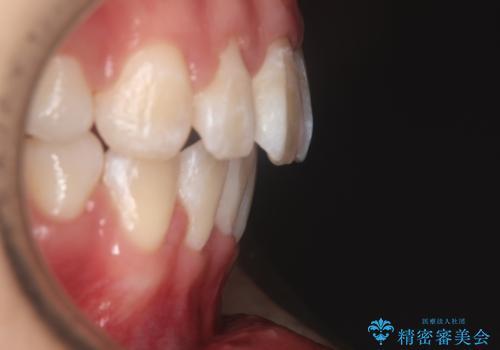

【審美装置】口元を下げたい

- 前歯のがたつきと口元を気にされて来院されました。

上下4番目の歯を抜歯してがたつきを改善しながら口元を下げる治療計画を立てました。

抜歯矯正をして口元を下げたことで、口元が下がりEラインが大変綺麗になりました。

矯正期間も1年9ヶ月と比較的短期間で終了することができました。